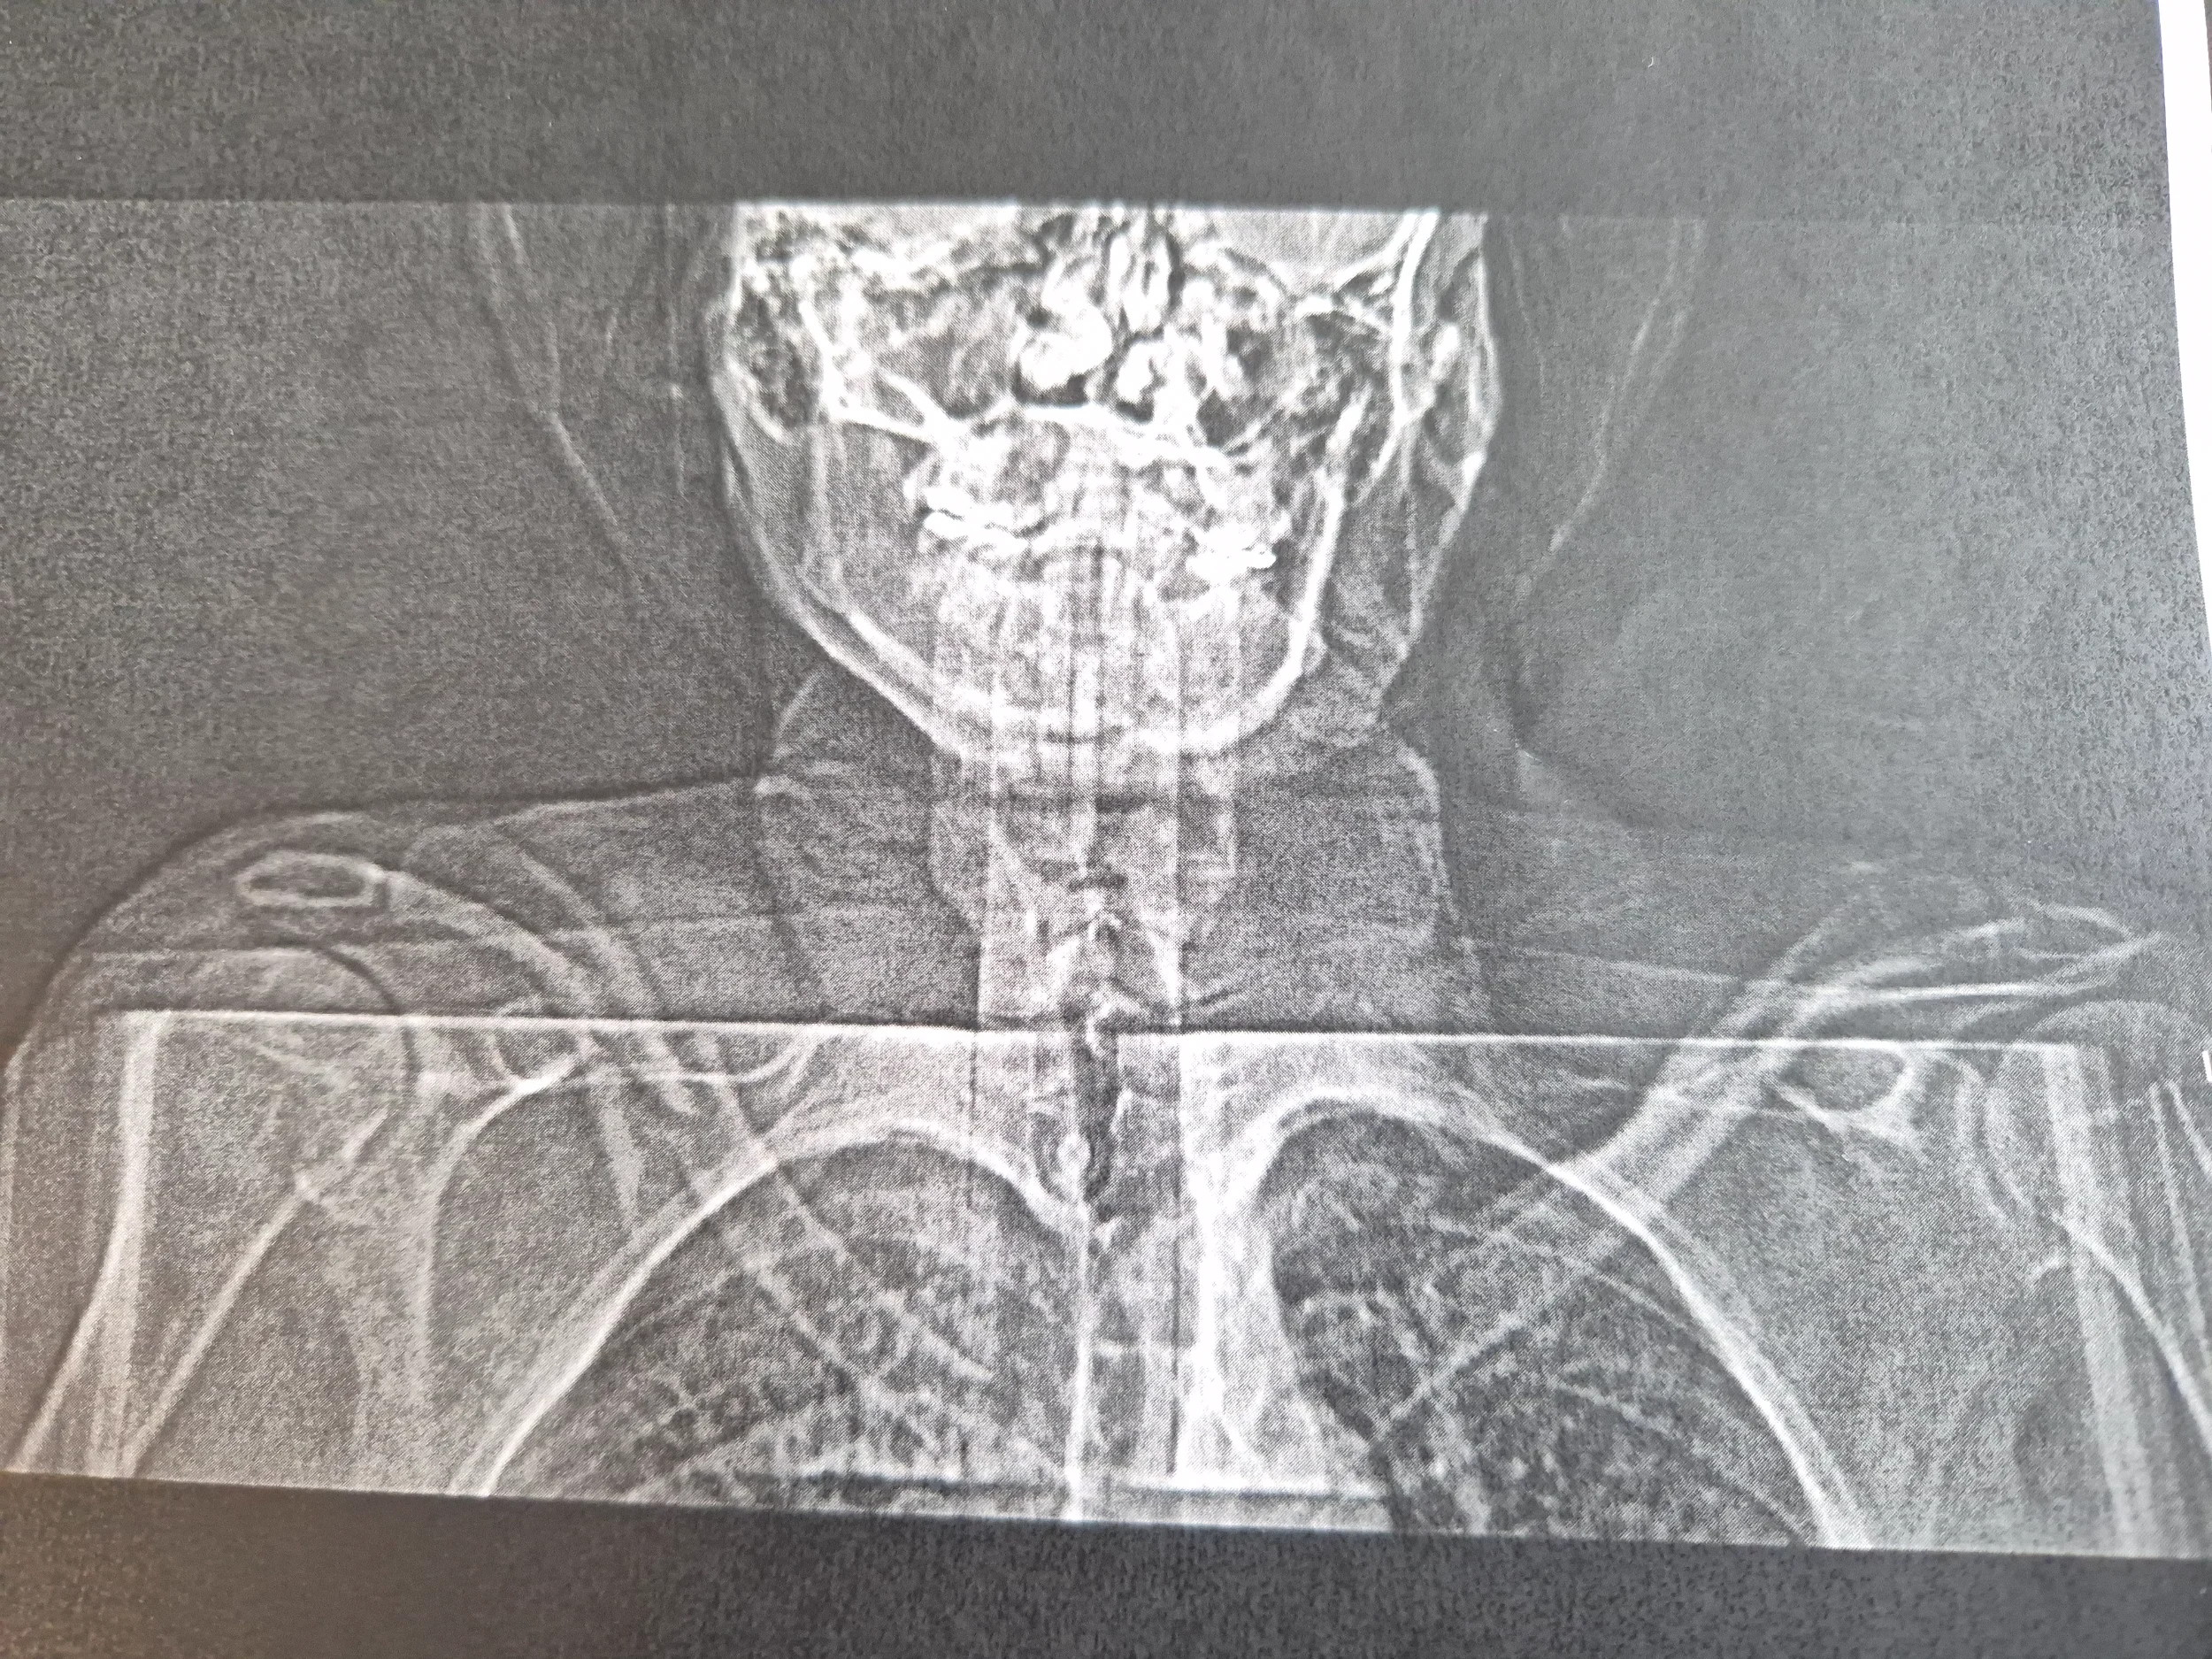

Sätt iaf inte in diskproteser mellan L4-S1 om du får problem.Enda (?) som är bra med misär-krascher är att man får tag i CT-bilder som täcker större delen av kroppen så man kan se lite detaljer på gamla skador :-)

Så här kommer ytterligare lite misärbilder:

Först 5 st 30 år gamla frakturer i bröstryggen efter att ha blivit påkörd av en bilist när jag cyklade. Fraktur på TH 1, 4, 5, 6 och 7 varav 5 och 6 var krossade enligt operationsberättelsen. Hade stag inopererade mellan TH3 och TH8 under tre år tills allt hade läkt.

Nästa bild innehåller 2 eller kanske egentligen 3 misärer.

1: Diskarna mellan kotorna L4-L5 och L5-S1 är i princip borta efter tidigare diskbråck. Normalt skall det vara ungefär lika stort avstånd mellan dessa som det är mellan L4 och L3 ovanför. På köpet har jag blivit 2 cm kortare.

2 & 3: Jag fick protes i vänster höft efter att min brutna ihopskruvade lårbenshals ledde till nekros i höftledskulan så att den delade i två delar. Sen sattes det in en protes med fel dimension och på så dåligt sätt att protesstammen i benet fick bytas ut. Vid om-operationen såg läkaren att muskeln gluteus medius inte såg så livskraftig ut. I bilden syns den i områdena som är inringade. På protessidan har nedre delen av muskeln förtvinat och ger således inte normal kraft. På mig funkar den ändå hyfsat, men jag får svårt att gå om jag bär mer än ca 10 kg i en ryggsäck. Tyvärr inget helt ovanligt fenomen vid höftprotesoperation och i mitt fall beror det troligen på att vissa av nerverna som styr muskeln har skadats vid operationen.